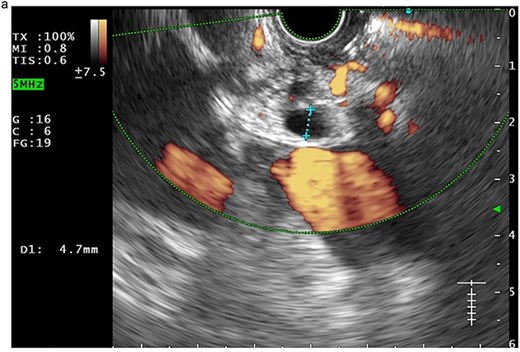

In view of the ongoing leakage and the hostile operative field, a third intervention was undertaken on postoperative day 24 following the second surgery. After multidisciplinary discussion, a combined surgical–endoscopic approach was undertaken in collaboration with internal medicine specialists. Intraoperative findings revealed dense adhesions from prior surgeries and a 0.5-cm perforation at the proximal duodenal stump, located near the ampulla of Vater. Initial endoscopic retrograde cholangiopancreatography (ERCP) was unsuccessful due to limited ampullary access; thus, EUS-CDS with ENBD placement was performed as an alternative strategy. From the duodenal bulb, the common bile duct (CBD) measured 4.7 mm on EUS, and Doppler confirmed no intervening vessels (Figs 4a and 4b). A 19-gauge EZ Shot 3 needle (Olympus) was used to puncture the extrahepatic bile duct, and bile aspiration followed by contrast injection confirmed correct positioning (Fig. 4c). A VisiGlide 2 angled guidewire (0.025 inch) was advanced into the right intrahepatic duct, and the tract was dilated using an ES dilator. A 7-Fr ENBD catheter was subsequently deployed across the choledochoduodenostomy under fluoroscopic guidance, achieving effective biliary drainage (Figs 4d and 4e). In addition, a 16-Fr Foley catheter was inserted into the duodenal perforation as a duodenostomy tube (Fig. 4f) for external drainage, and six closed wound vacuum drains were placed for peritoneal irrigation and drainage.